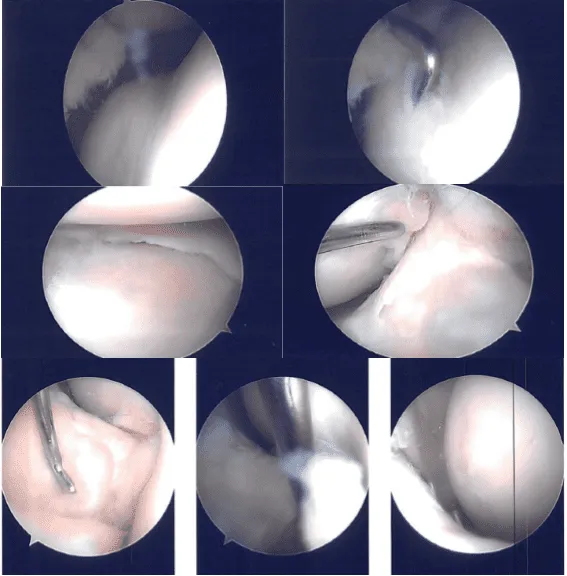

A lateral working portal was made through left-sided Incision. The scope was entered into a patellofemoral joint where arthritis was found on the medial and lateral facet of the patella as well as in the trochlea.

The scope was entered into medial femoral condyle where medial femoral condyle arthritis was found. There was a medial meniscus tear along the anterior body. The scope was entered into the intercondylar notch where ACL was Intact. The scope was entered into the lateral tibiofemoral Joint.

A horizontal flap tear of the right anterior margin of the posterior body of the lateral meniscus along with the medial fraying of the medial margin of the lateral meniscus was found. Medial entry portal was made with direct access to the lateral meniscus. The scope was entered and findings were reconfirmed.

Intraoperative Images

The medial meniscectomy was performed using a shaver. Medial femoral chondroplasty was also confirmed using a shaver. Cyclops lesion was found on the ACL lateral Insertion. The cyclops was then excised using a shaver.

The scope was entered into the lateral compartment where the tears were reconfirmed. Excision of the medial horizontal flap was done using straight biter.

Cribbing of the lateral meniscus was done using a shaver. Balanced margins were achieved. There was no arthritis in the lateral femoral condyle. Now the attention was focused onto the patellofemoral joint.

Chondroplasty of the patellar medial and lateral facet as well as the trochlea was performed. There were grade 2 to grade 3 lesions. There was a medial shelf plica which was excised completely.

Final findings were checked and reconfirmed from the other portal also. The final pictures were saved. The knee was irrigated thoroughly. Closure was done using nylon #4-0.